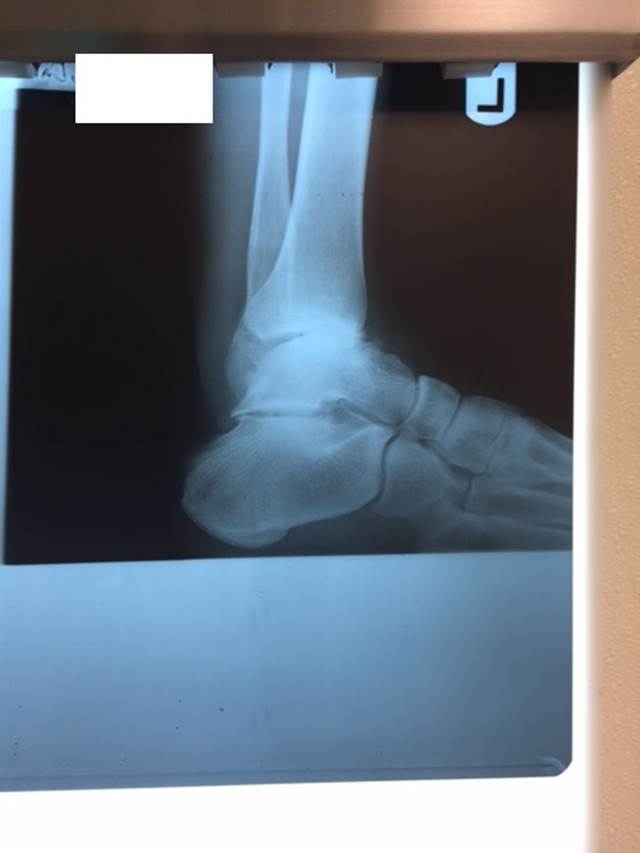

"Surgical misadventure" by another surgeon about 8 years ago. The wrong fixation was used for a flatfoot repair, & the deformity was not corrected. Patient came in with severe foot & ankle pain, with no arch at all. She was unable to play with her grandchild because the pain was so bad, & because she felt unsteady. The old hardware was removed, a lateral calcaneal lengthening osteotomy was performed along with a medial column/1st ray realignment. The ankle was painfully arthritic, & patient elected a total ankle replacement vs. an ankle fusion. She is now able to walk pain free & play with her grandchildren!